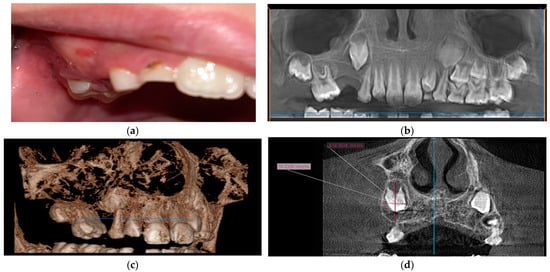

2.2.3. Case 3